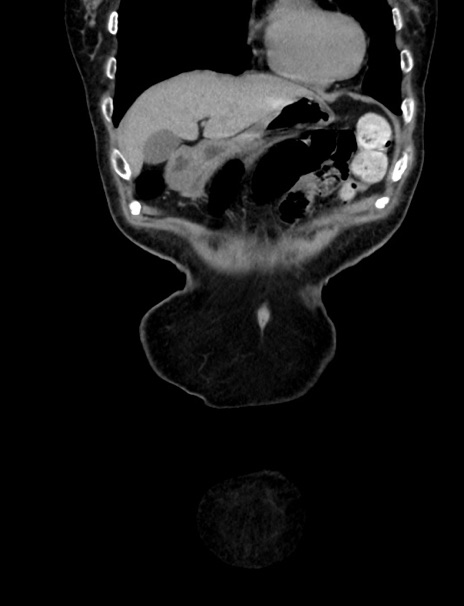

横断像

【症例】70歳代 女性

【主訴】心窩部痛

【現病歴】延髄病変の精査・加療にて神経内科入院中。本日より心窩部痛あり。

【身体所見】右下腹部を中心に圧痛と反跳痛あり。

【データ】WBC 10900、CRP 0.02